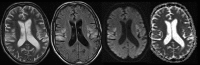

A 48-year-old man was admitted for workup of stroke-like symptoms and generalised tonic-clonic seizures. History and examination revealed that the patient had background diagnoses of type 2 diabetes mellitus, epilepsy and had suffered a temporal lobe infarct 3 years ago. The unusual presentation and physical findings, along with subsequent MRI findings led to a diagnosis of mitochondrial myopathy, encephalopathy, lactic acidosis and stroke-like episodes (MELAS). MELAS is a mitochondrial disorder typified by the aforementioned symptoms, and is typically diagnosed in the first two decades of life.